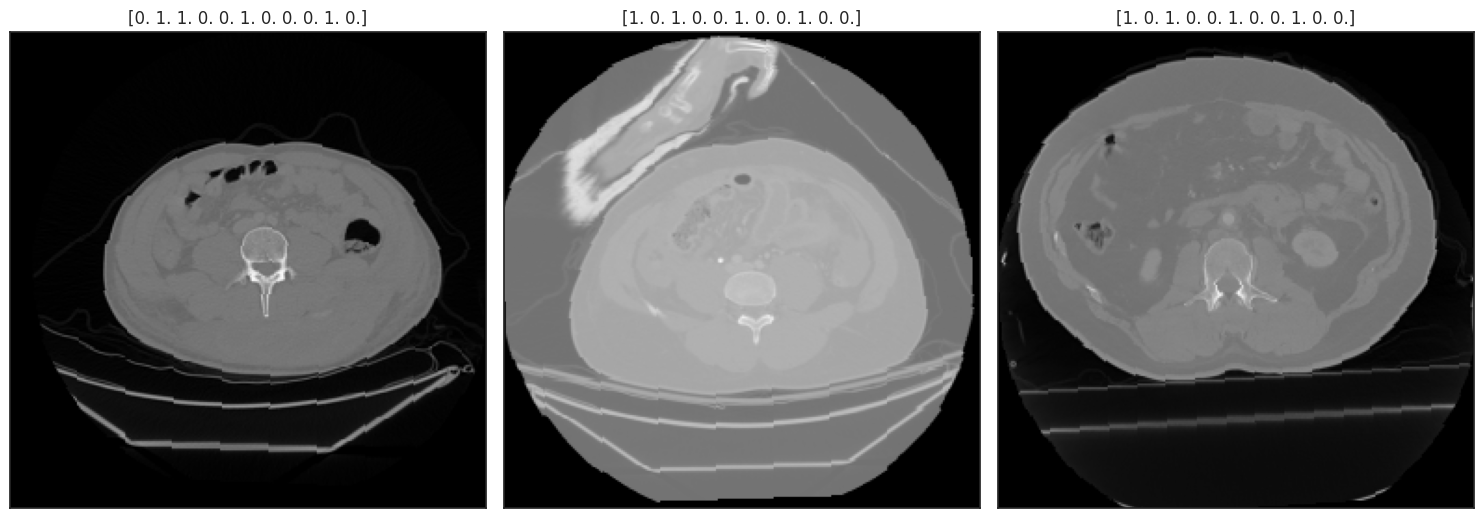

RNSA 2023 Abdominal Trauma Detection